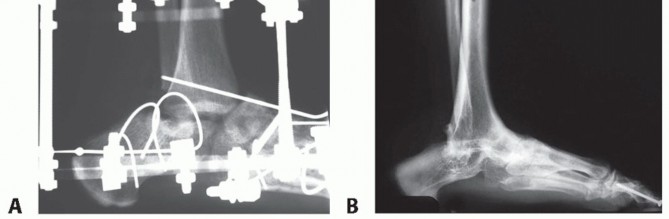

An ankle series of radiographs will reveal the extent of the bone loss, the extent of AVN, and the location of internal fixation hardware in the talus and plafond (FIG 3).

FIG 3 • A,B. Anterior and lateral x-ray of ankle with infected nonunion of talus. The ankle had a draining sinus. The talar body is avascular and the talar head has bone lysis around the two fixation screws. The plafond has erosion and destruction of the cartilage. There is reactive bone on the medial malleolus compatible with infection.*